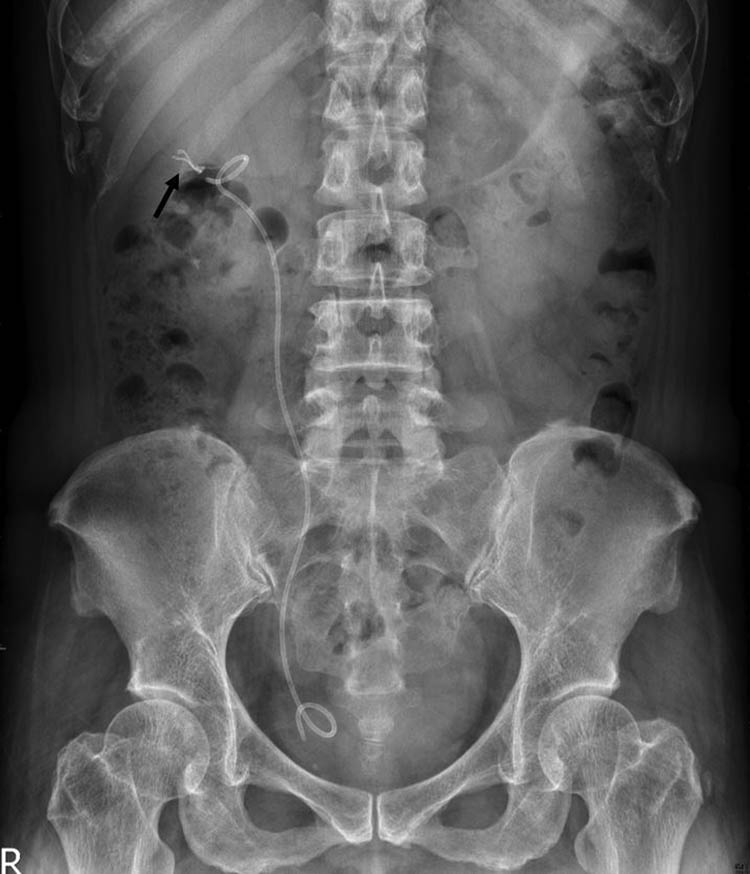

A plain radiograph of the kidneys, ureters, and bladder (KUB) showed a new radiopaque lesion in the right renal shadow compared with the pre-PCND plain film (Figure 1). This artifact was considered to be a retained ruptured guidewire or fragments of the PCND. Further CT imaging was performed to determine the precise anatomical location and the radiodensity of the object, which was revealed to be a curvilinear hyperdense coil within the upper pole parenchyma of the right kidney (Figure 2a–c). The radiologists judged that the coil could be the remnants of a guidewire used during the PCND procedure.

Post-PCND follow-up KUB show a new radiopaque lesion (arrow) in right kidney area.